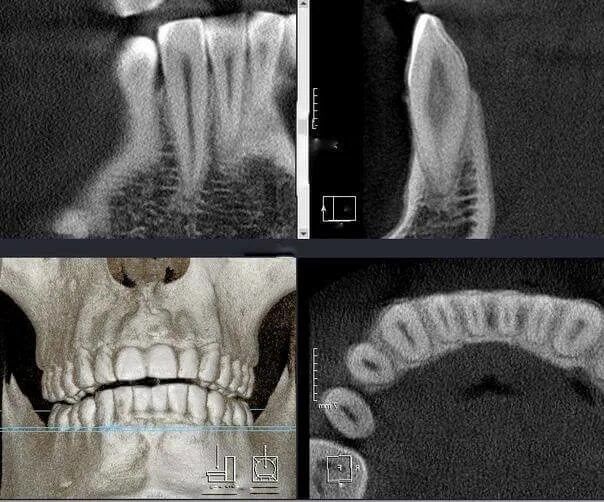

Кл кт